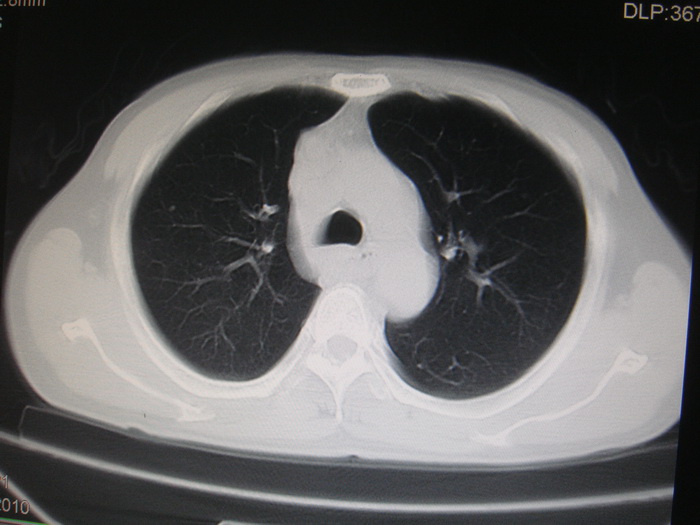

标题: CT28366:男性,45岁,偶尔发现右颈部肿块行胸部CT扫描。 [打印本页]

男性,45岁,偶尔发现右颈部肿块行胸部ct扫描。

两肺多发结节灶及纵膈淋巴结肿大考虑为转移

两肺多发性转移瘤,纵隔淋巴结转移。

两肺多发性转移瘤,纵隔淋巴结转移。食道中上段管壁似乎增厚,作相关检查。

两肺多发性转移瘤,前上纵隔淋巴结转移。